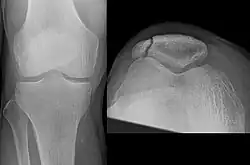

Types

The patella can break in various ways depending on the way it is injured, and into two or more pieces.[1] Types include transverse, with one fracture line and is the most common type,[5] marginal, osteochondral and the rare vertical type, or stellate, where a direct compression force gives rise to a comminuted pattern.[5][7] Patella fractures can be further classified as displaced, where the broken ends of bone do not line up correctly and separate by more than 2mm, or undisplaced and stable where pieces of bone remain in contact with each other.[1][7] If fragments of patella bone stick out from the skin it is known as an open patella fracture, and closed if the overlying skin is intact.[1]

Transverse fracture of patella

Comminuted fracture of patella

Osteochondral fracture of patella

Vertical patella fracture